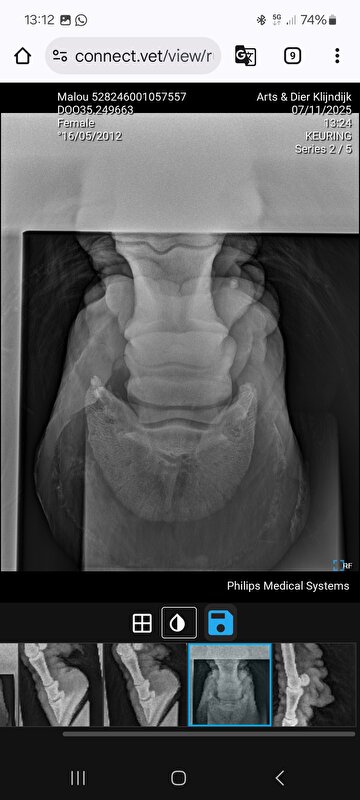

. Na aanleiding van de filmpjes die in dit topic staan gaan we voor de zekerheid nu foto's maken van de voorbenen.